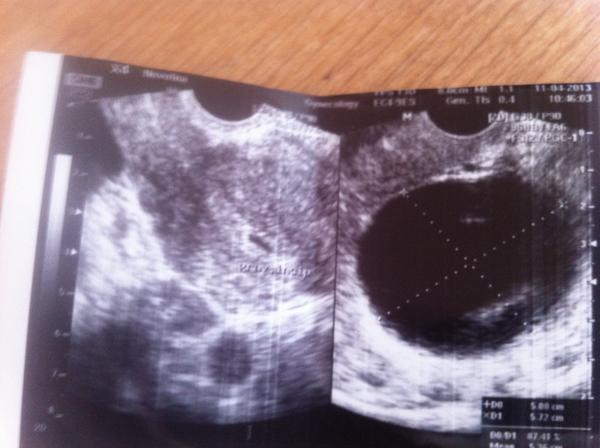

Holky je to těhu?

Holky myslite že je to těhu?dr nevi jiste a ja jsem nervozní!vim že nejste dr ale třeba mate zkušenost

no mohlo by to být v začátku. Záleží kdy ji to dostala naposled. Budu držet palce aby to dopadlo dobře

dle mého to těhu je,, teprve na počátku, ale je. nechápu ale, že doktor si není jistý. zkus zajít na nějaké gynek.oddělení do nemocnice třeba. a nebo jestli tě vyšetří jiný doktor. .... držím palce, aby to těhu bylo a ty jsi se mohla radovat z mimíska.

To nalevo je cista